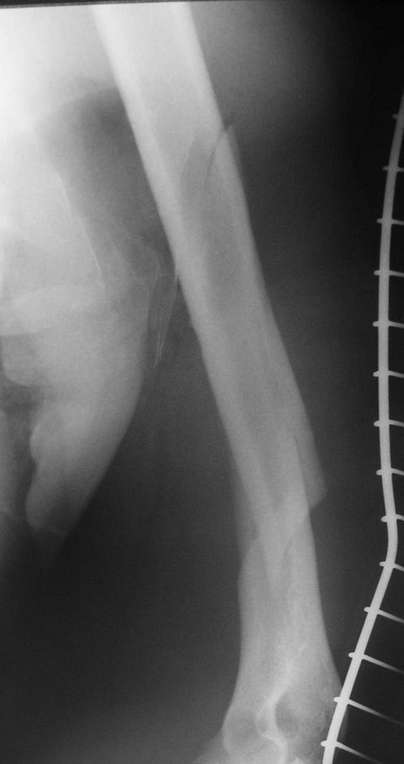

Красиво и быстро?! - две пластины + 18 шурупов.

Идеальная репозиция?! -На снимочке A-P проeкции видна "зазубрина" по суставной поверхности, латеральный снимок - тоже не идеально.

Множество мелких FB в кости.